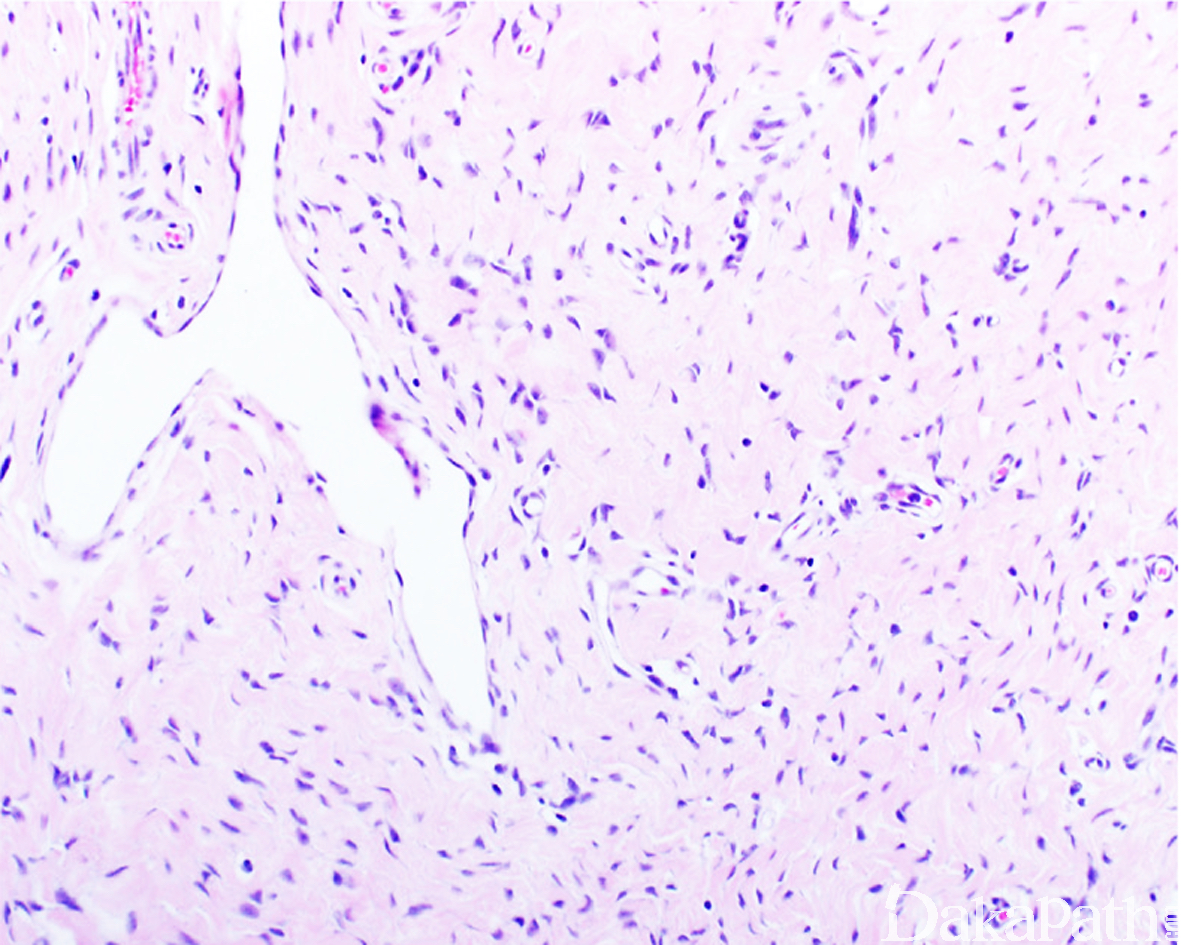

原始间叶组织呈结节状分布,由幼稚的短梭形、卵圆形或星状细胞排列成呈疏松的漩涡状、巢状或宽带状包被于富于血管的黏液性基质之间;

瘤细胞形态均教温和,核异型性轻微,罕见核分裂象;